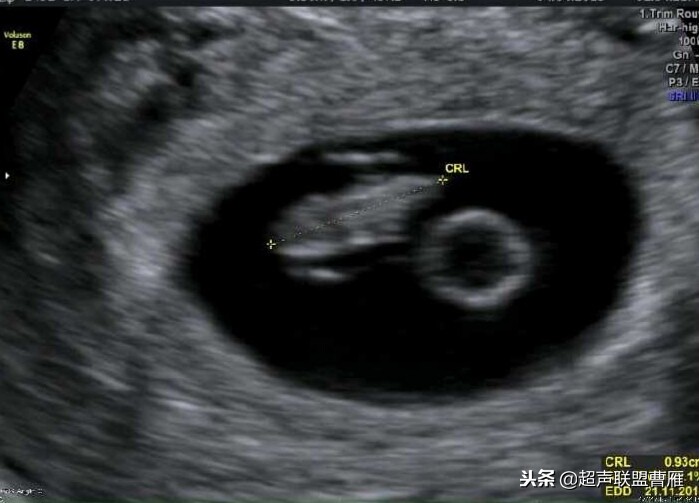

妊娠40天,见到卵黄囊、胚极及心管搏动, HCG12800U/L。

卵黄囊高分辨超声图像,妊娠40天

早孕 胚芽 卵黄囊

5周+ 、6周+ 声像图

孕7周左右(胚芽11mm 卵黄囊)

胎芽 卵黄囊 心管搏动信号

宫内早孕 (7周左右)